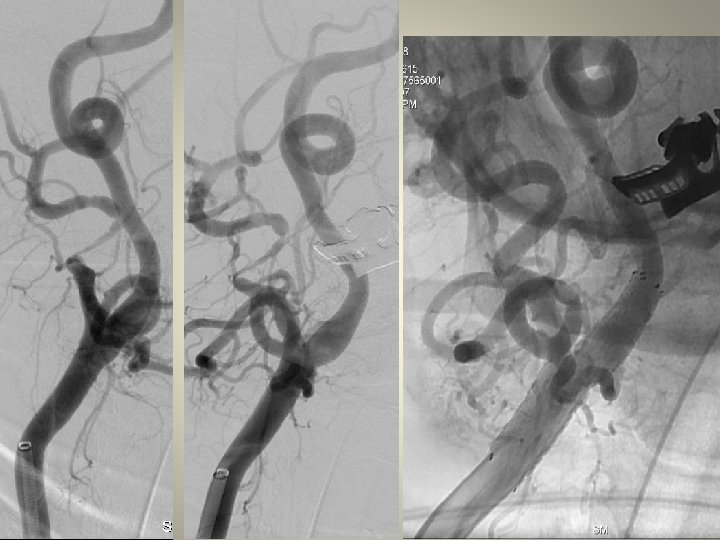

Neden stent? Distal emboli koruma

Neden stent? Eş zmanlı komplikasyon idaresi

Ülsere plak olgu